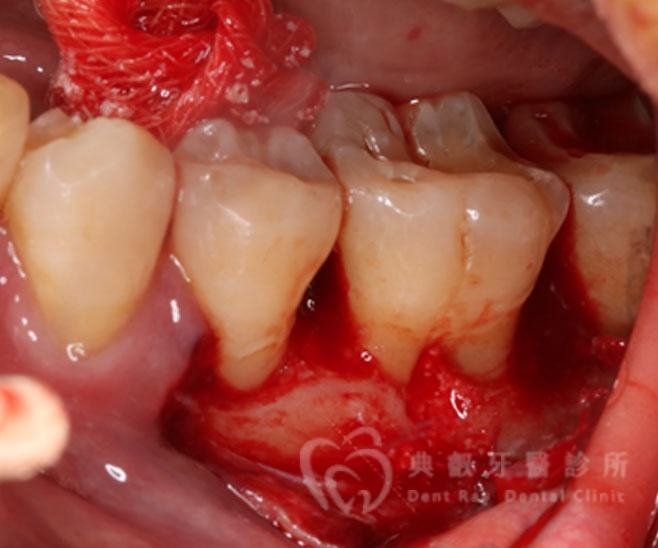

牙周手術案例二

術後兩個月